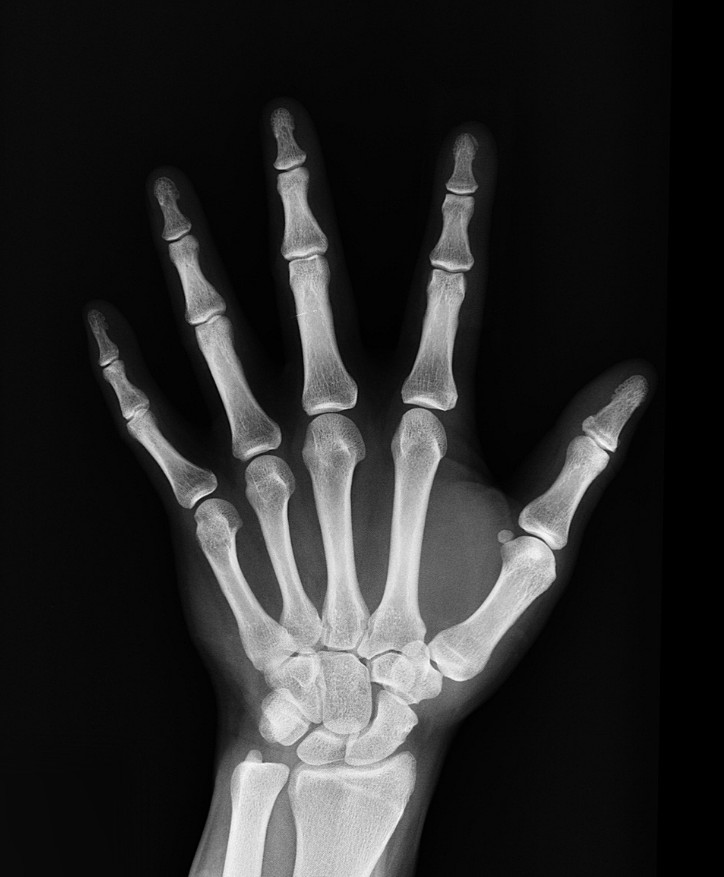

뼈는 살아있는 조직으로 매일 새롭게 만들어지고 사라지기를 반복합니다.

하지만 사실 뼈는 끊임없이 **골형성(새 뼈 만들기)**과 **골흡수(묵은 뼈 제거)**를 반복하는 살아있는 조직입니다.

골다공증은 뼈가 약해져 작은 충격에도 쉽게 골절되는 질환입니다.